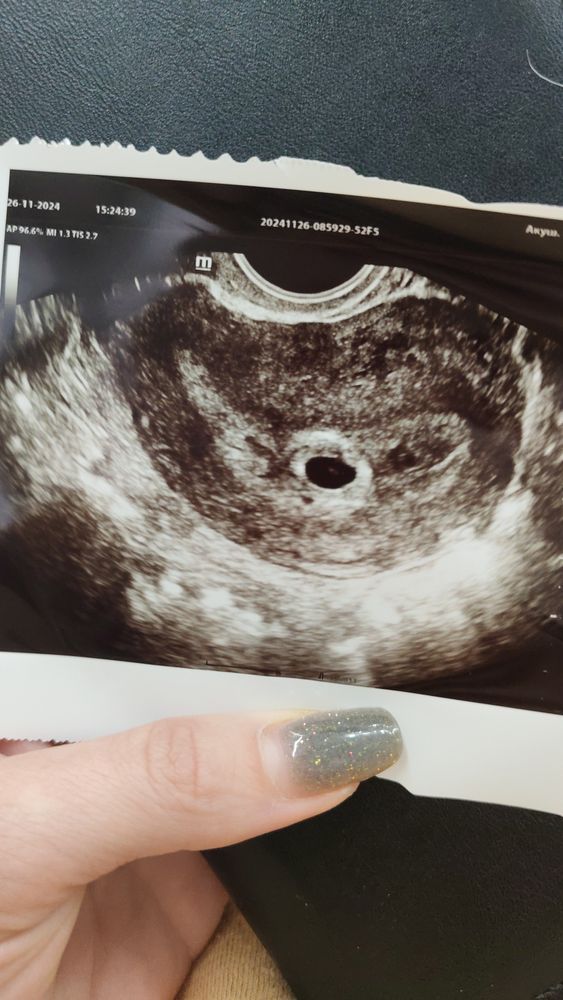

Наденька, отслеживала и овуляцию и тесты были положительные на 10дпо на 19дпо первое узи там еле разглядела пя но было 2-3мм , потом на 26 день , 26 ноября второе узи пя 7мм но эмбриона еще не было , был желточный мешок. И вот 19 декабря.. Эмбрион 6мм по узи в жк и ставят 6нелель , в платной в этот же день вообще сказали 4мм.. 🙄 и там де вот взяли хгч , сейчас пришел анализ, просто если 6 недель это типо оплодотворение попадает на ноября, а у меня уже узи было с пя в 2-3мм от 19 числа и положительные тесты с 10числа . и сердцебиение не сказали , мерцание есть, сердцебиение нет , типо рано... Но как рано если 9нелель должно быть, даже ладно пусть погрешностью будет неделя и 8.. Все равно уже должно быть. Тут читала что плод бывает медленно замирает и вместо сердцебиения как раз мерцание .

Алена, да я выжидаю дни и пойду на узи вот последний мне дали в жк снимок 19 декабря.. И 26 ноября предыдущий 26 не было видно эмбриона но она мне показывала желточный мешок был и сказала вот там будет эмбрион